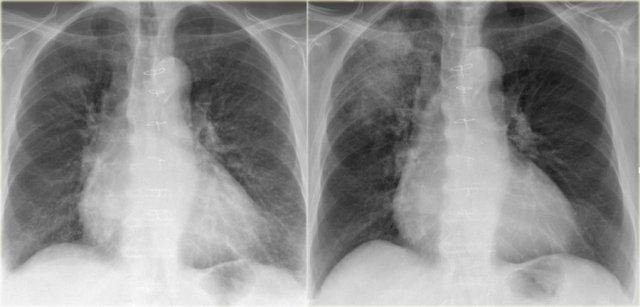

Kiểu hình ảnh dạng lưới trong suy tim sung huyết

Hãy quan sát các hình ảnh rồi tiếp tục đọc.

Các dấu hiệu bao gồm:

- Phim cũ bình thường ở bên trái.

- Kiểu hình ảnh dạng lưới đặc biệt ở vùng đáy phổi. Có thể thấy một số đường Kerley B.

- Tim to.

- Tràn dịch màng phổi bên trái.

- Mạch máu phổi nổi bật hơn so với phim cũ.

Dựa trên các dấu hiệu này, chúng ta có thể kết luận đây là suy tim sung huyết.

Đây là kiểu hình ảnh mô kẽ phổ biến nhất trên phim X-quang ngực thẳng.

Phù mô kẽ thường biểu hiện dưới dạng lưới.

Đôi khi có thể thấy các đường Kerley B.